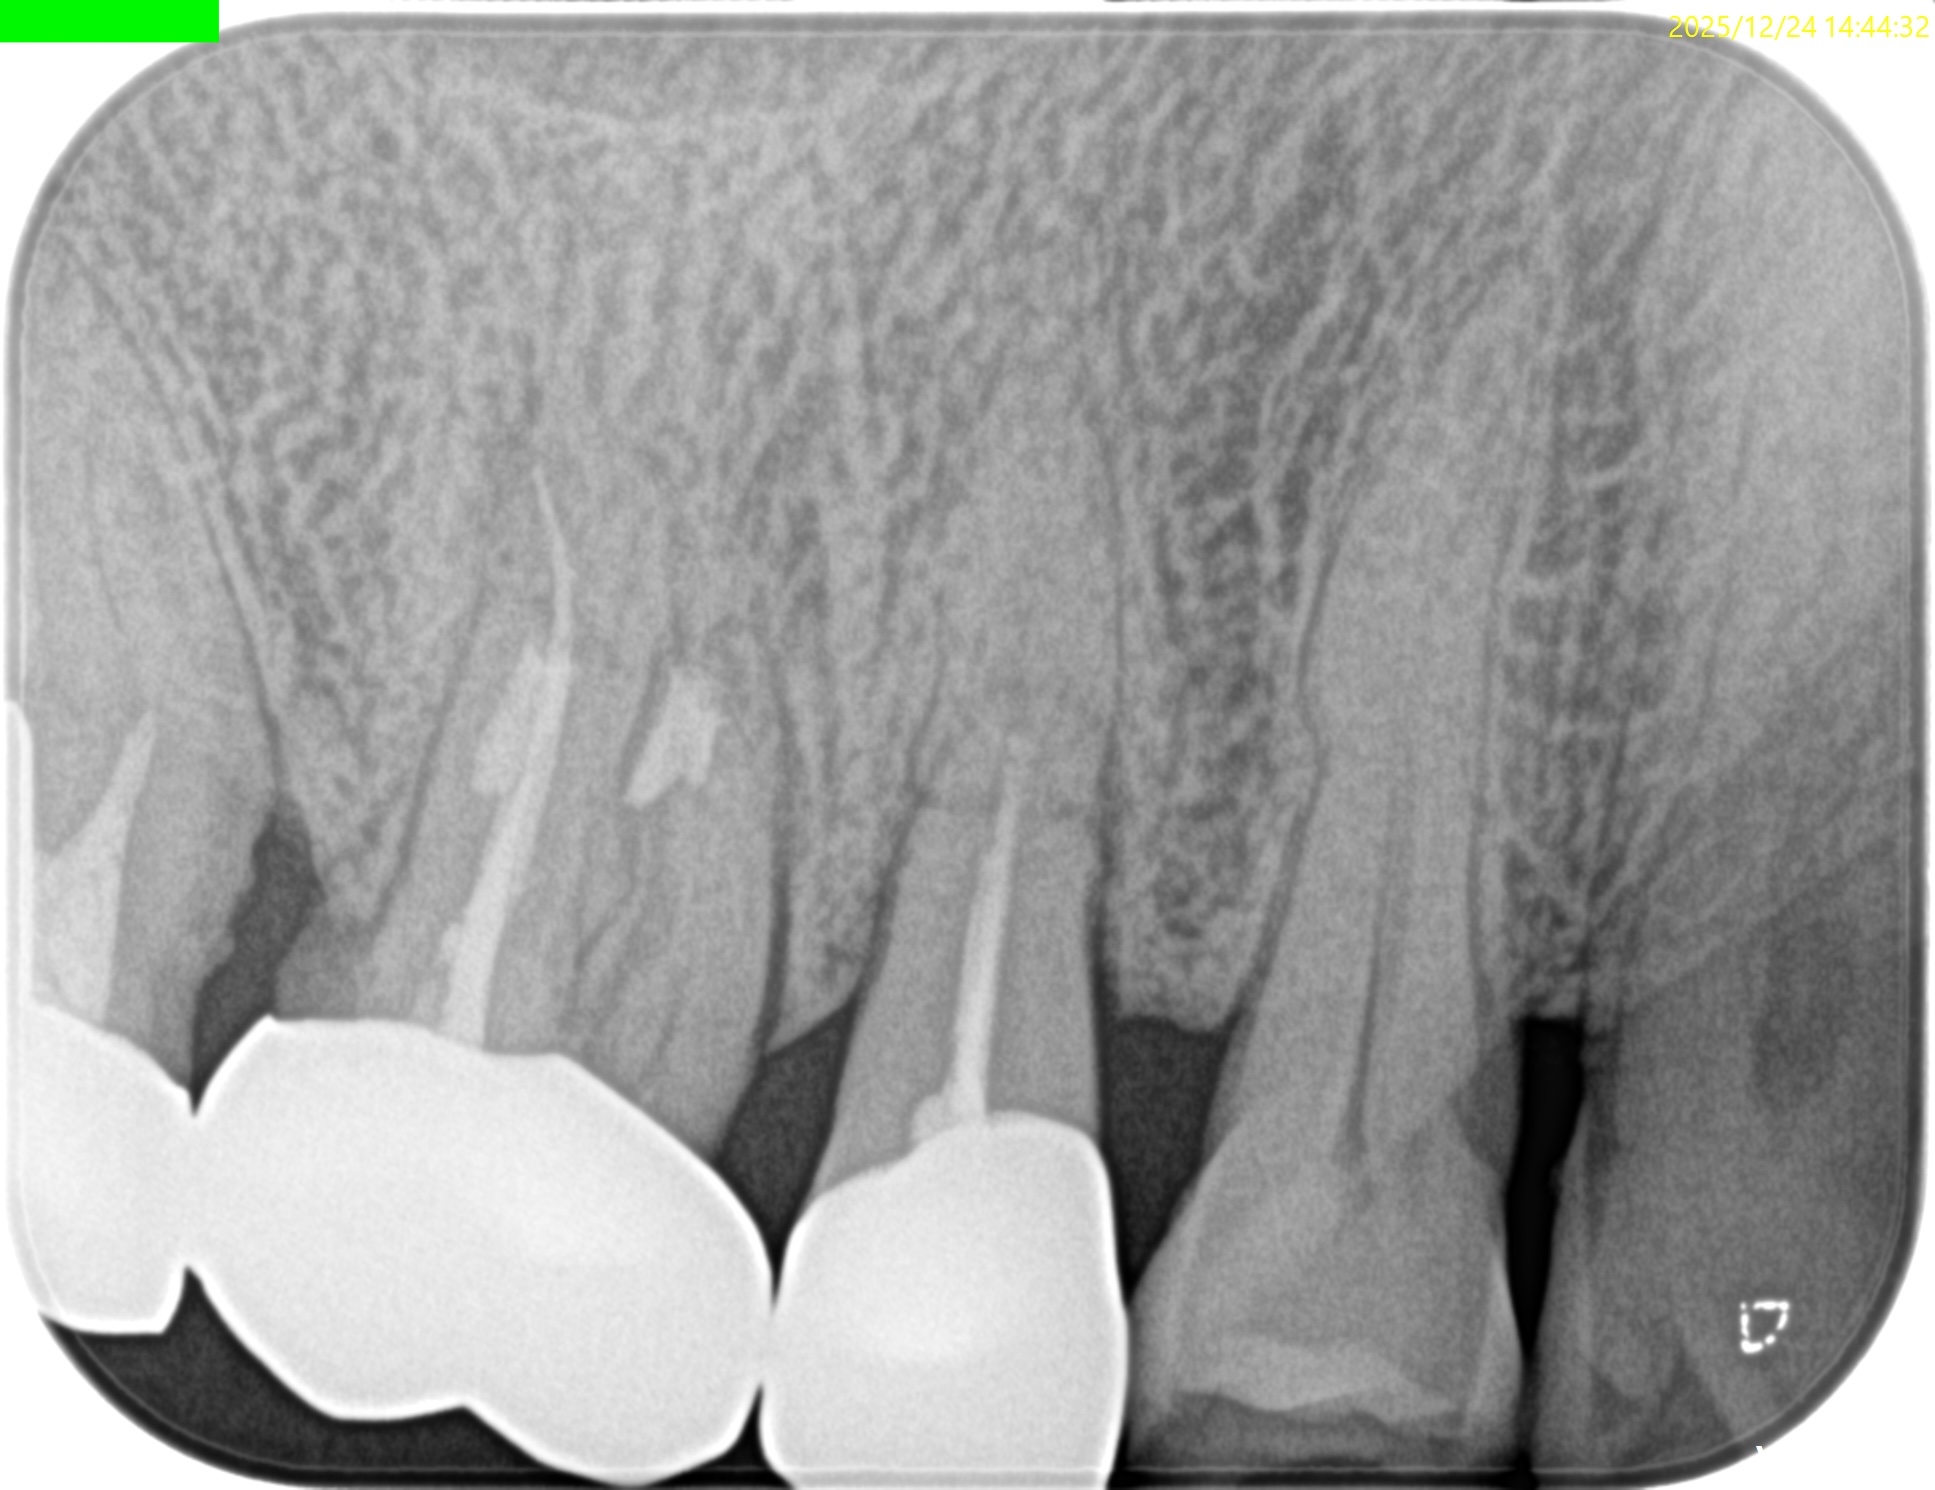

#4 RCT 1yr recall(2025.12.24)

臨床症状, 術前の歯根膜腔隙の拡大はともに消失した。

ということで、#4の経過観察も終了でいいだろう。